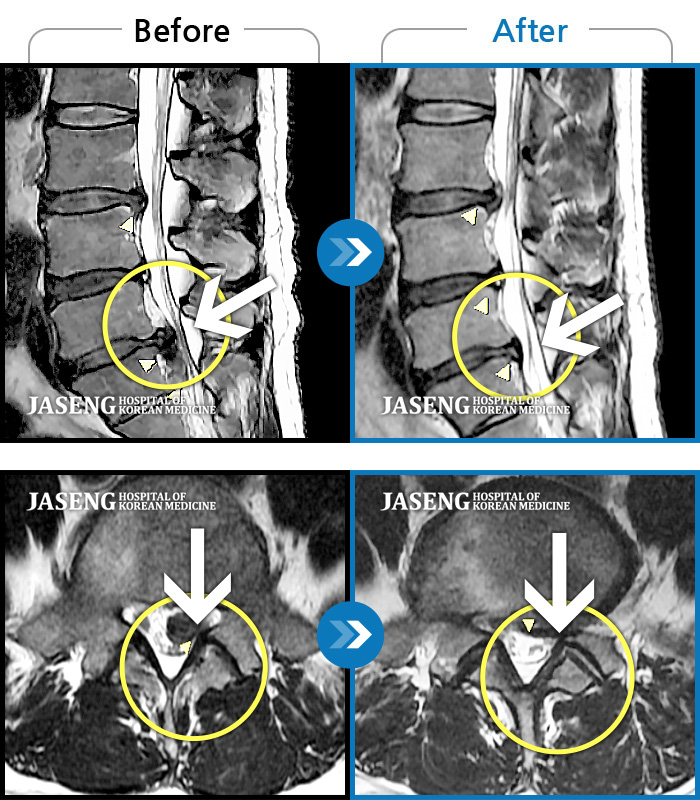

내일이면 퇴원이다. 3월부터 주위에서 허리통증 치료 잘 한다는 통증의학과ㆍ신경외과ㆍ정형외과 병원 3곳을 돌아다니며 허리 신경주사 12번 ,도수치료 10번, 물리치료 등등 정알 여러가지를 받았다. 그러나 치료와 처방 받은 진통제만으로는 일상생활을 하기가 많이 힘들었다. X레이 사진으로 확인한 척추 전방전위증은 결국은 수술을 받아야 한다고 하였다.

전방전위 대해 알아보다가 자생병원 홈페이지에서 김상돈 병원장님이 임상치료 하셨다는 것을 보고 잠시의 망설임도 없이 전화 예약하고 입원 하게 되었다.

MRI 검사로 정확한 진단을 시작으로 병원장님의 치료를 2주간 받았다. 친절한 설명과 따뜻한 배려로 정말 마음 편하게 치료 받을수 있었다.

극심한 통증으로 입원 첫날에 맞은 진통제 주사는 더 이상 필요없게 되었다 다시한번 김상돈 병원장님께 감사 드립니다.